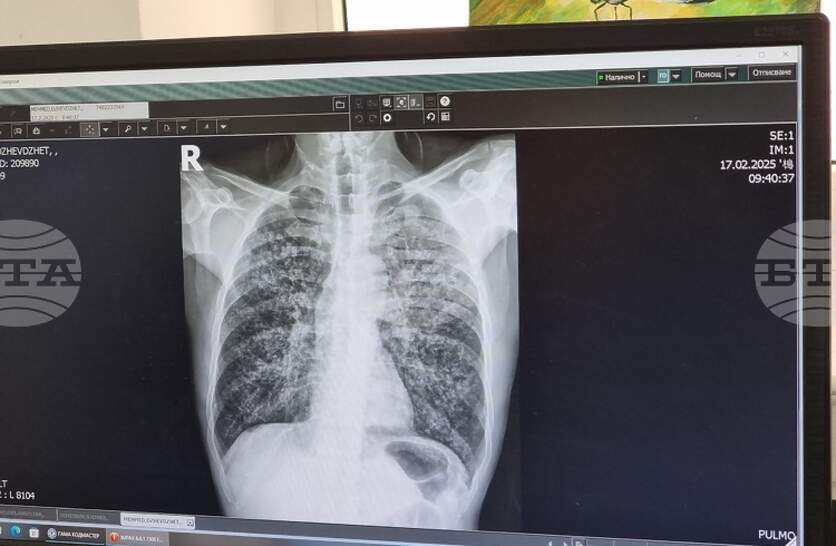

Безплатни прегледи и изследвания за туберкулоза ще се извършват в пневмо-фтизиатричното отделение на областната Многопрофилна болница за активно лечение (МБАЛ) „Свети Пантелеймон“ в Ямбол от 8 до 12 декември, съобщиха от лечебното заведение. Скринингът за заболяването ще се извършва от 12:00 до 15:00 часа в петте дни. Седмицата на отворените врати е част от кампания на Министерството на здравеопазването в рамките на Националната програма за превенция и контрол на туберкулозата в България за периода 2021 – 2025 година. От началото на тази година в област Ямбол с регистрирани 18 случая на туберкулозна инфекция. От тях три са от последните дни – 23-годишна жена и децата – на 11 месеца и на 4 години, които в момента се лекуват в болница в София, каза директорът на Регионалната здравна инспекция д-р Радостина Калчева. Туберкулозата засяга предимно хора с нисък социален и здравен статус, затова в кампанията активно се включват и ромски медиатори, посочи д-р Калчева. През изминалата 2024 г. в региона са регистрирани 19 случая, а през 2023 г. заболелите са били 23-ма, допълни директорът на здравната инспекция.